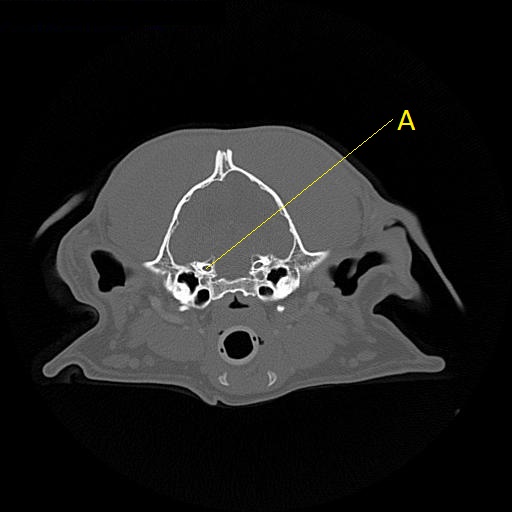

Q. Identify the structure labeled below:

A. Canal for the trigeminal nerve